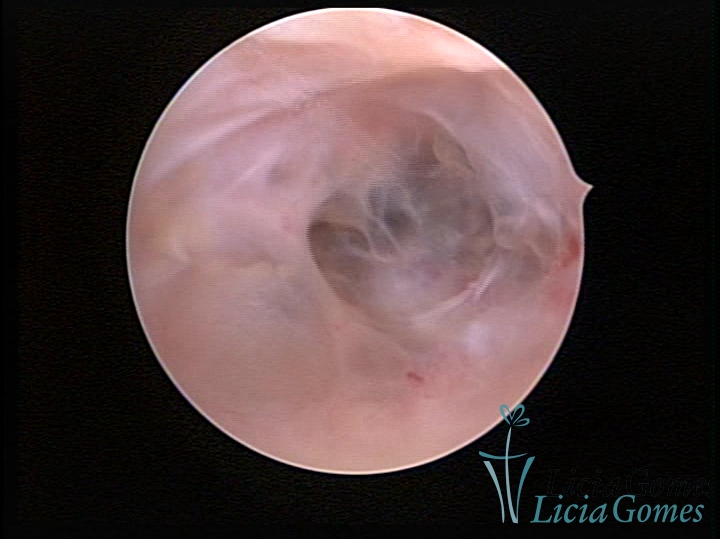

FIBROUS SYNECHIA

Uterine synechiae are scars (adherence) between the surface of the uterine walls, which may occur after the surgical procedure, uterine curettage, or after an inflammatory process in the uterine cavity (endometritis), which may lead to menstrual changes, infertility and obstetric complication such as abortion and premature birth.